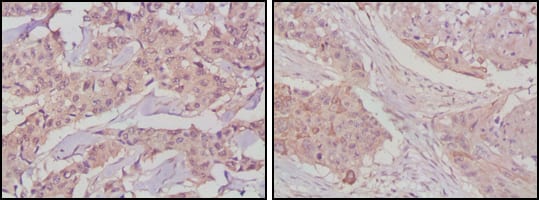

Immunohistochemical analysis of paraffin-embedded human lung cancer (left) and breast cancer tissues (right) using GSK3B mouse mAb with DAB staining.